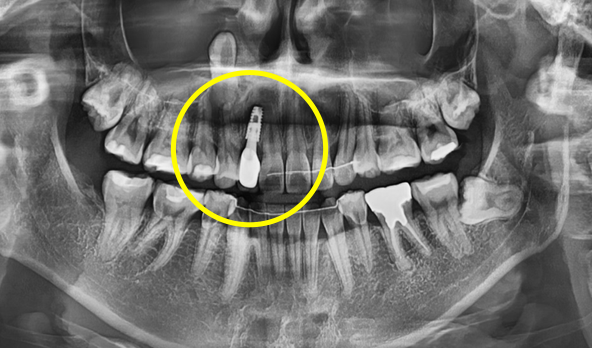

3D 모의 수술로 최적 식립 위치 계산

3차원 CT사진과 구강스캐너를 이용하여

미리 가상의 수술을 거쳐서 수술 위치를 정하고

수술 후 상부 위치까지 예측해서

미리 보철물을 만들어 두었다가

당일 수술 후 보철물을 붙이는

네비게이션 임플란트 방식입니다.